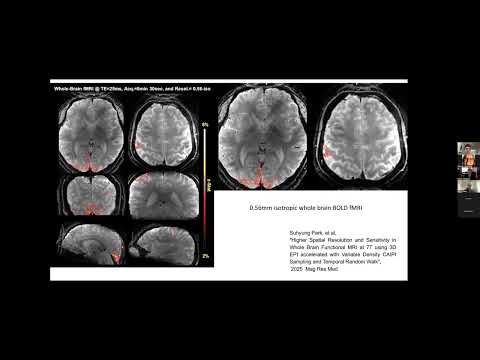

Join the Connectome 2.0 Dissemination Workshop on June 3, 2026, 9 AM-4 PM EST at the MGH Martinos Center. Learn about ultra-high gradient MRI, diffusion MRI, connectivity, and microstructural imaging using the Connectome 2.0 scanner. Program details: connectome2.martinos.org/2026-workshop/